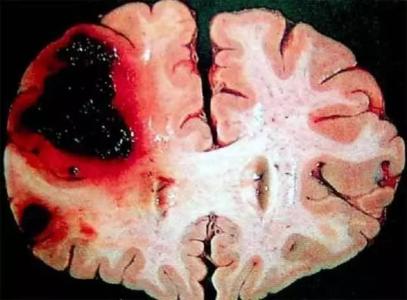

腦溢血,也就是我們通常所說的腦出血。腦溢血是非常嚴重的疾病,在急性期腦溢血的死亡率可以達到百分之30到40%。

腦溢血,系指非外傷性腦實質(zhì)內(nèi)的出血。絕大多數(shù)是高血壓病伴發(fā)的腦小動脈病變在血壓驟升時破裂所致,稱為高血壓性腦出血。